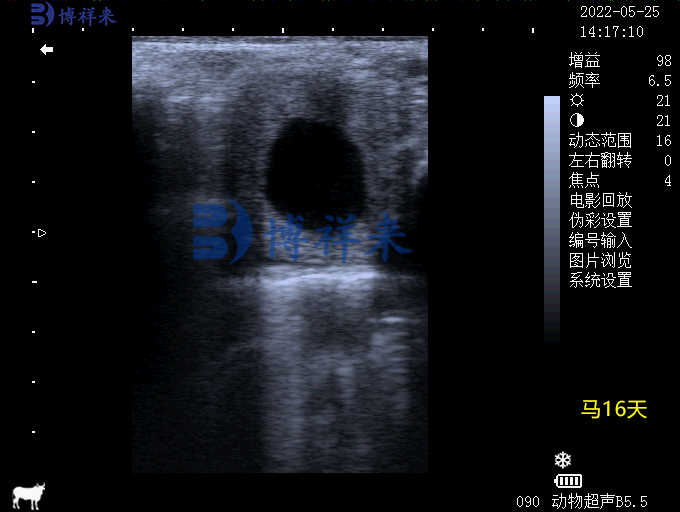

马妊娠16天B超图像

- 未孕母马:子宫壁均匀,无囊泡结构。

- 妊娠母马:显示圆形或椭圆形无回声暗区,伴随胚胎发育逐渐出现胎心搏动。